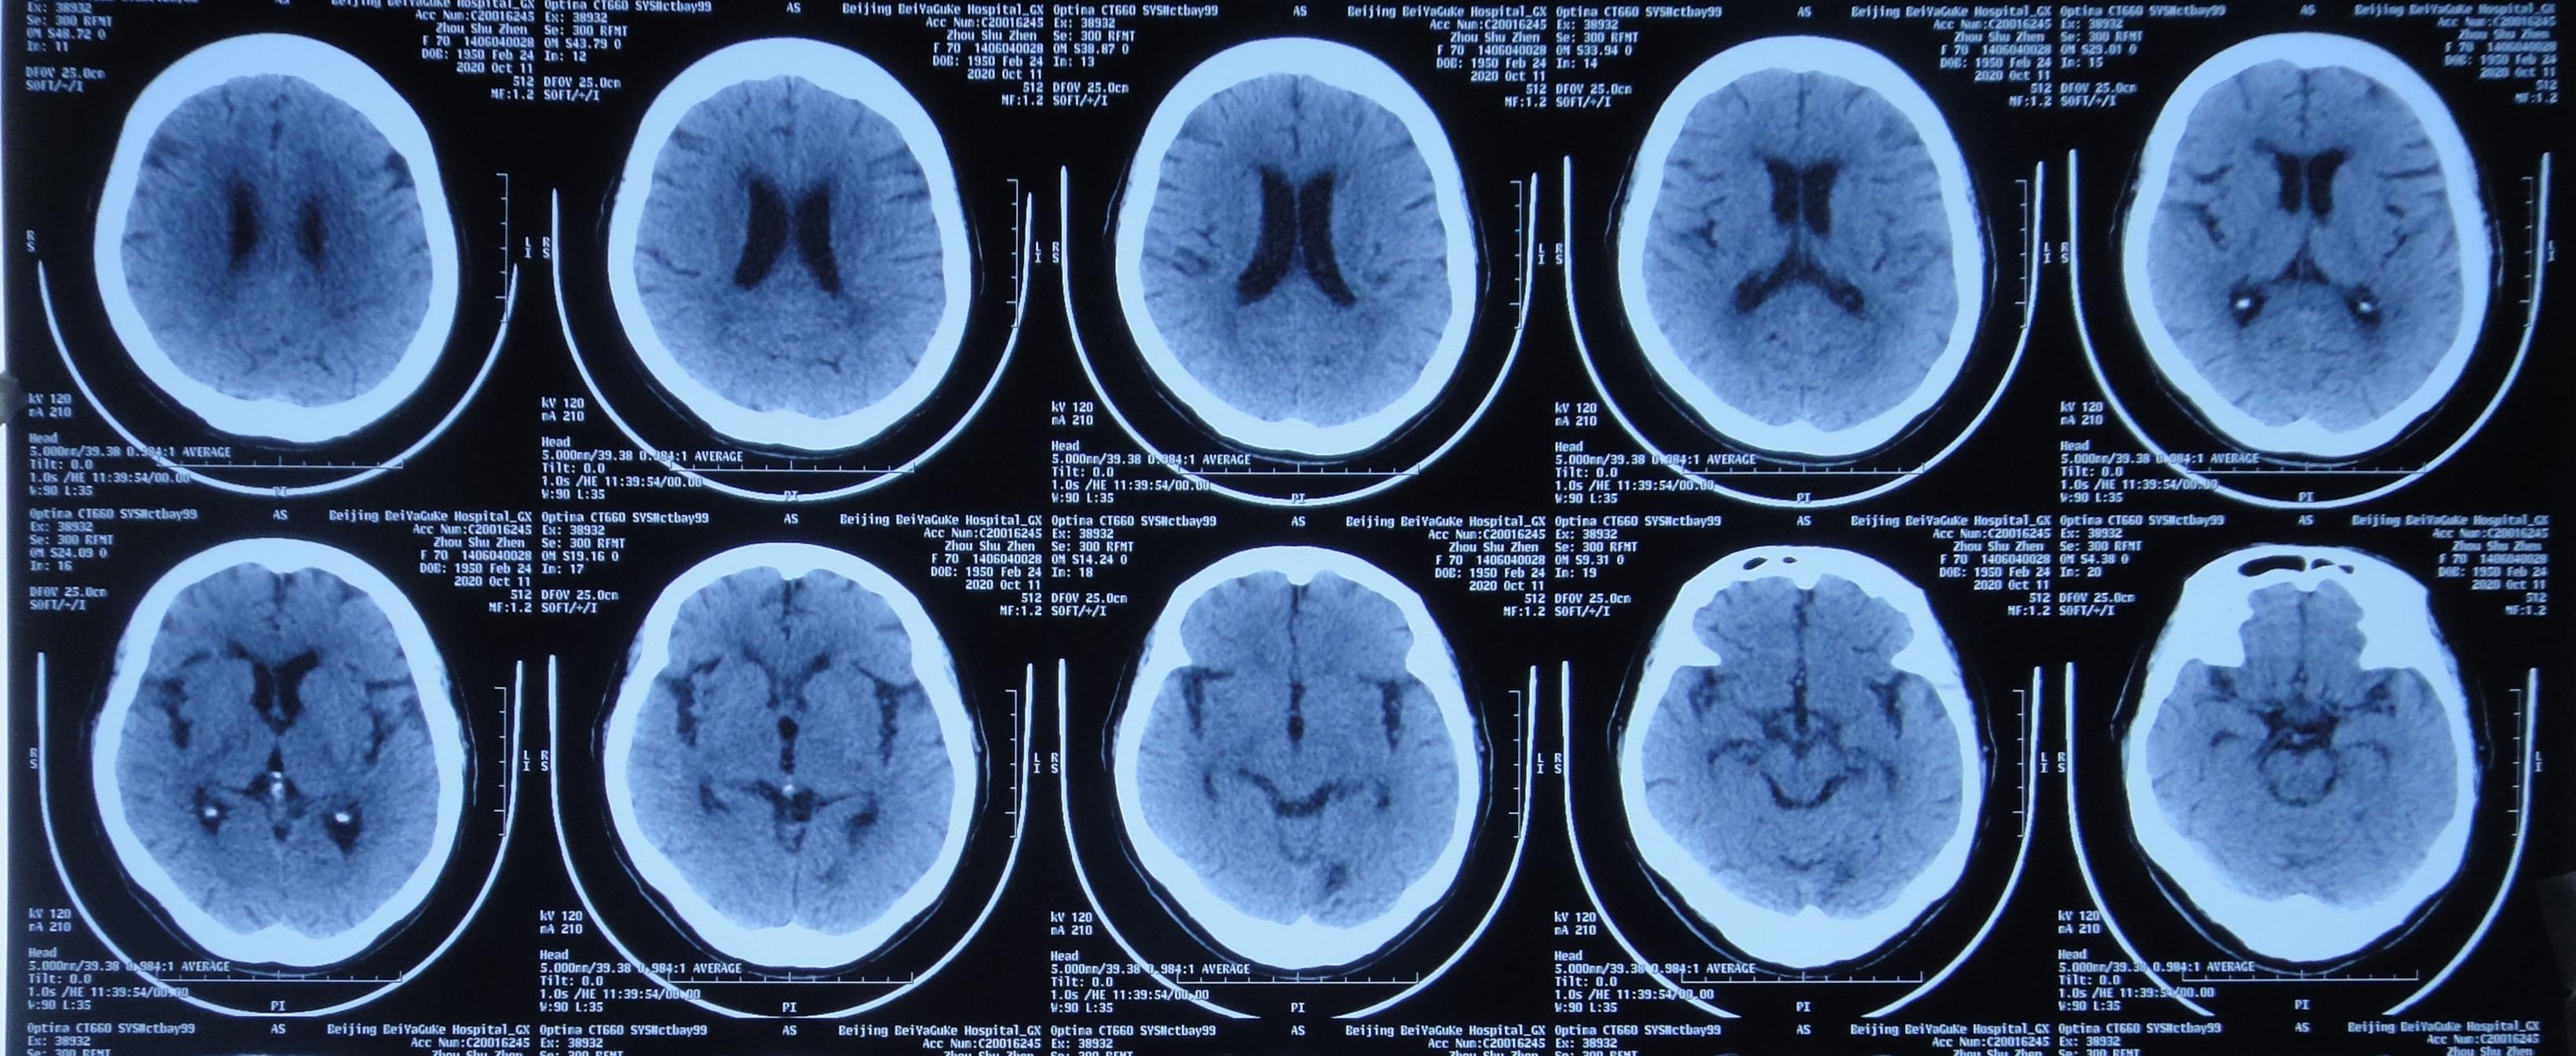

2020年10月11日(入脑脊液科第41天,拔除脑室引流管后第14天,即第二次颈椎病术后第59天)颈部伤口愈合良好,复查头颅CT:未见异常( 图-17 ),于是转回中医骨伤科继续康复锻炼及治疗。

图-17: 2020年10月11日头颅CT